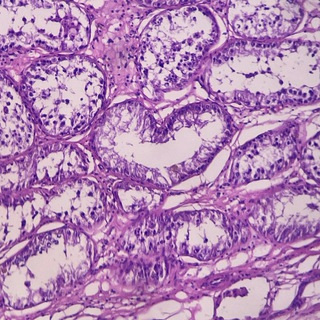

Группа ветеринарного патолога, который рассказывает о необычных и обычных случаях из своей лабораторной практики.

#ветеринария #гистология #патология